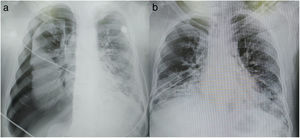

Se trata de un varón de 64 años con antecedentes de diabetes mellitus, quien presentó astenia, adinamia, odinofagia, fiebre y tos seca acompañada de disnea de medianos esfuerzos. Se realizó hisopado nasofaríngeo con resultado positivo para la infección por SARS-CoV-2, en la tomografía de tórax se observó parénquima pulmonar con múltiples imágenes en vidrio despulido y consolidaciones bilaterales indicativas de proceso infeccioso (COVID-19). Se encontraba en categoría 5 según la clasificación radiológica de afectación pulmonar por coronavirus COVID-19 Reporting and Data System ?CO-RADS?1. Fue hospitalizado para brindarle apoyo con oxígeno mediante cánulas de alto flujo, sin obtener respuesta adecuada. A los 5 días aumenta el trabajo respiratorio, presentando datos de hipoxemia, por lo que se decide intubación endotraqueal para apoyo ventilatorio mecánico. Los signos vitales en terapia intensiva fueron: temperatura 39°C, frecuencia cardíaca de 111lpm, presión arterial de 140/70mmHg, 24rpm y saturación de oxígeno del 84%. Los resultados de laboratorio más relevantes fueron los siguientes: hemoglobina 12,3g/dl, hematocrito 36,6%, plaquetas 584×103/ul, tiempo de protrombina 11,8s, INR 1,06, tiempo de tromboplastina parcial 36,9s. A pesar del tratamiento médico continúa con saturación 70-85% y acidosis respiratoria descompensada. Se decide colocar al paciente en posición de decúbito prono, con mejoría inmediata de la saturación de oxígeno al 92%. En la radiografía de tórax de control se visualiza neumotórax espontáneo derecho (60%), por lo que se realizó toracostomía con colocación de sonda pleural en posición de decúbito prono debido a la situación respiratoria crítica (PaO2/FiO2: 64mmHg, PEEP: 14cmH2O), que imposibilitaba cambiar al paciente a posición supina (fig. 1 a).

Durante el procedimiento, las medidas de protección personal utilizadas fueron: mascarilla N95, cubrebocas con careta plástica, guantes de látex estériles, goggles, overol, bata estéril y botas desechables. Se indica la presencia de 3 profesionales de atención sanitaria en el cuarto de aislamiento (2 cirujanos, una enfermera), paciente en posición de decúbito prono, flexión del antebrazo sobre el brazo, protección de hiperextensión del hombro, con elevación a 45° con rollo debajo del hemitórax derecho. Teniendo como referencia anatómica la punta de la escápula, se realiza la demarcación del sitio quirúrgico (línea axilar anterior, media, posterior, quinto y sexto espacio intercostal derecho), asepsia y antisepsia, se infiltra anestésico local (lidocaína al 2%), se prepara la unidad de drenaje torácico (kit de drenaje pleural Drentech™ Compact), sello de agua 40ml, solución salina al 0,9% más 10ml de hipoclorito de sodio. Se realiza una incisión de 1cm en el sexto espacio intercostal, línea axilar media derecha, se diseca de forma roma por planos y se realiza pausa espiratoria al ventilador mecánico. Mediante la técnica de la pinza se accede al espacio pleural a la altura del quinto espacio intercostal, utilizando una pinza uterina Bozeman para direccionar el drenaje torácico con mayor seguridad (opciones: Thoracoport™ 10,5mm, pinzas Kelly o Kocher). Se introduce una sonda pleural 32Fr pinzada en su extremo distal dirigida hacia el ápex o el vértice posterior del espacio pleuropulmonar; es conectada a la unidad de drenaje torácico, con un sistema aspiración continua que llega a un tanque de vacío exclusivo para el área COVID con motores que generan temperaturas de 100°C (fig. 2). Se realiza una radiografía de tórax de control, que evidencia la adecuada reexpansión pulmonar (fig. 1 b). Continúa el tratamiento y el seguimiento del paciente.